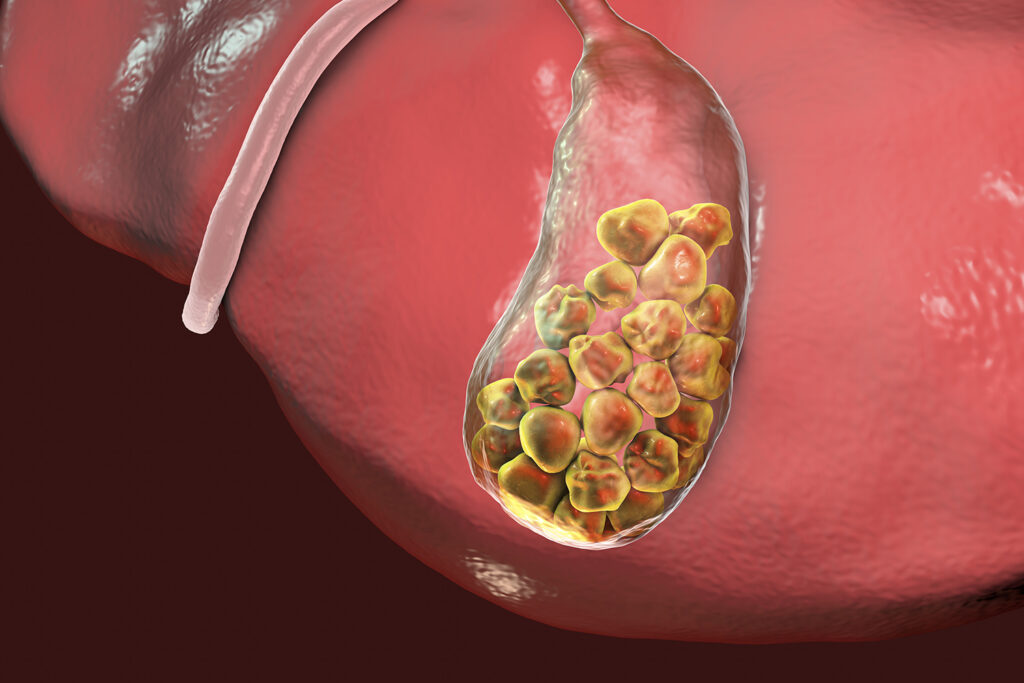

The gallbladder is a small organ that stores bile, a digestive fluid produced by the liver. Over time, gallstones—hardened deposits of bile—can form and lead to blockages, infections, and inflammation.

This can result in painful symptoms and digestive issues, often requiring surgical removal of the gallbladder.